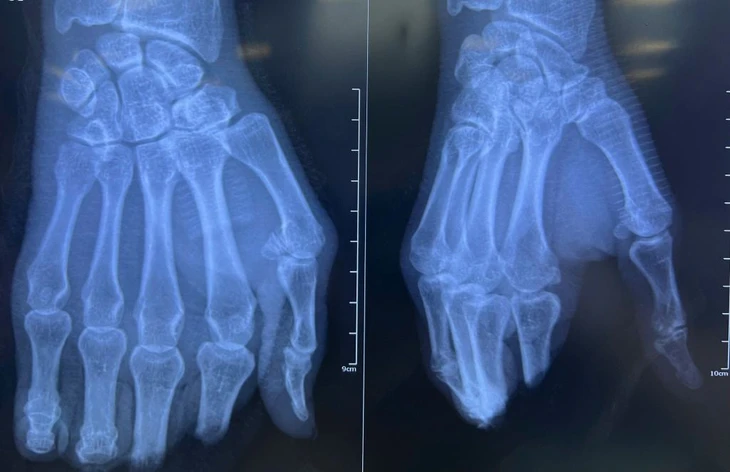

Sau 8 tiếng phẫu thuật nối tay, các ngón tay của bệnh nhân đã hồng hào, tưới máu tốt - Ảnh: Bệnh viện cung cấp

Bệnh nhân nhập viện trong tình trạng đứt lìa các ngón II, III, IV, V bàn tay phải. Qua thăm khám, bác sĩ xác định đây là ca bệnh phức tạp do vị trí đứt tại khớp liên đốt gần và đốt xa, mô mềm giập nát nghiêm trọng.

Ê kíp phẫu thuật đã thực hiện kỹ thuật vi phẫu suốt 8 giờ liên tục để nối lại 4 ngón tay, quá trình phẫu thuật bao gồm cố định lại xương, nối mạch máu, thần kinh và nối gân gấp duỗi từng ngón tay.

Bác sĩ Nguyễn Cao Viễn, Phó trưởng khoa ngoại chấn thương - chỉnh hình Bệnh viện Nhân dân 115, cho biết hiện tại các ngón tay đã hồng hào, tưới máu tốt, kỳ vọng người bệnh sẽ sớm hồi phục để có thể tiếp tục tập vật lý trị liệu nhằm nhanh chóng phục hồi chức năng vận động của các ngón tay.